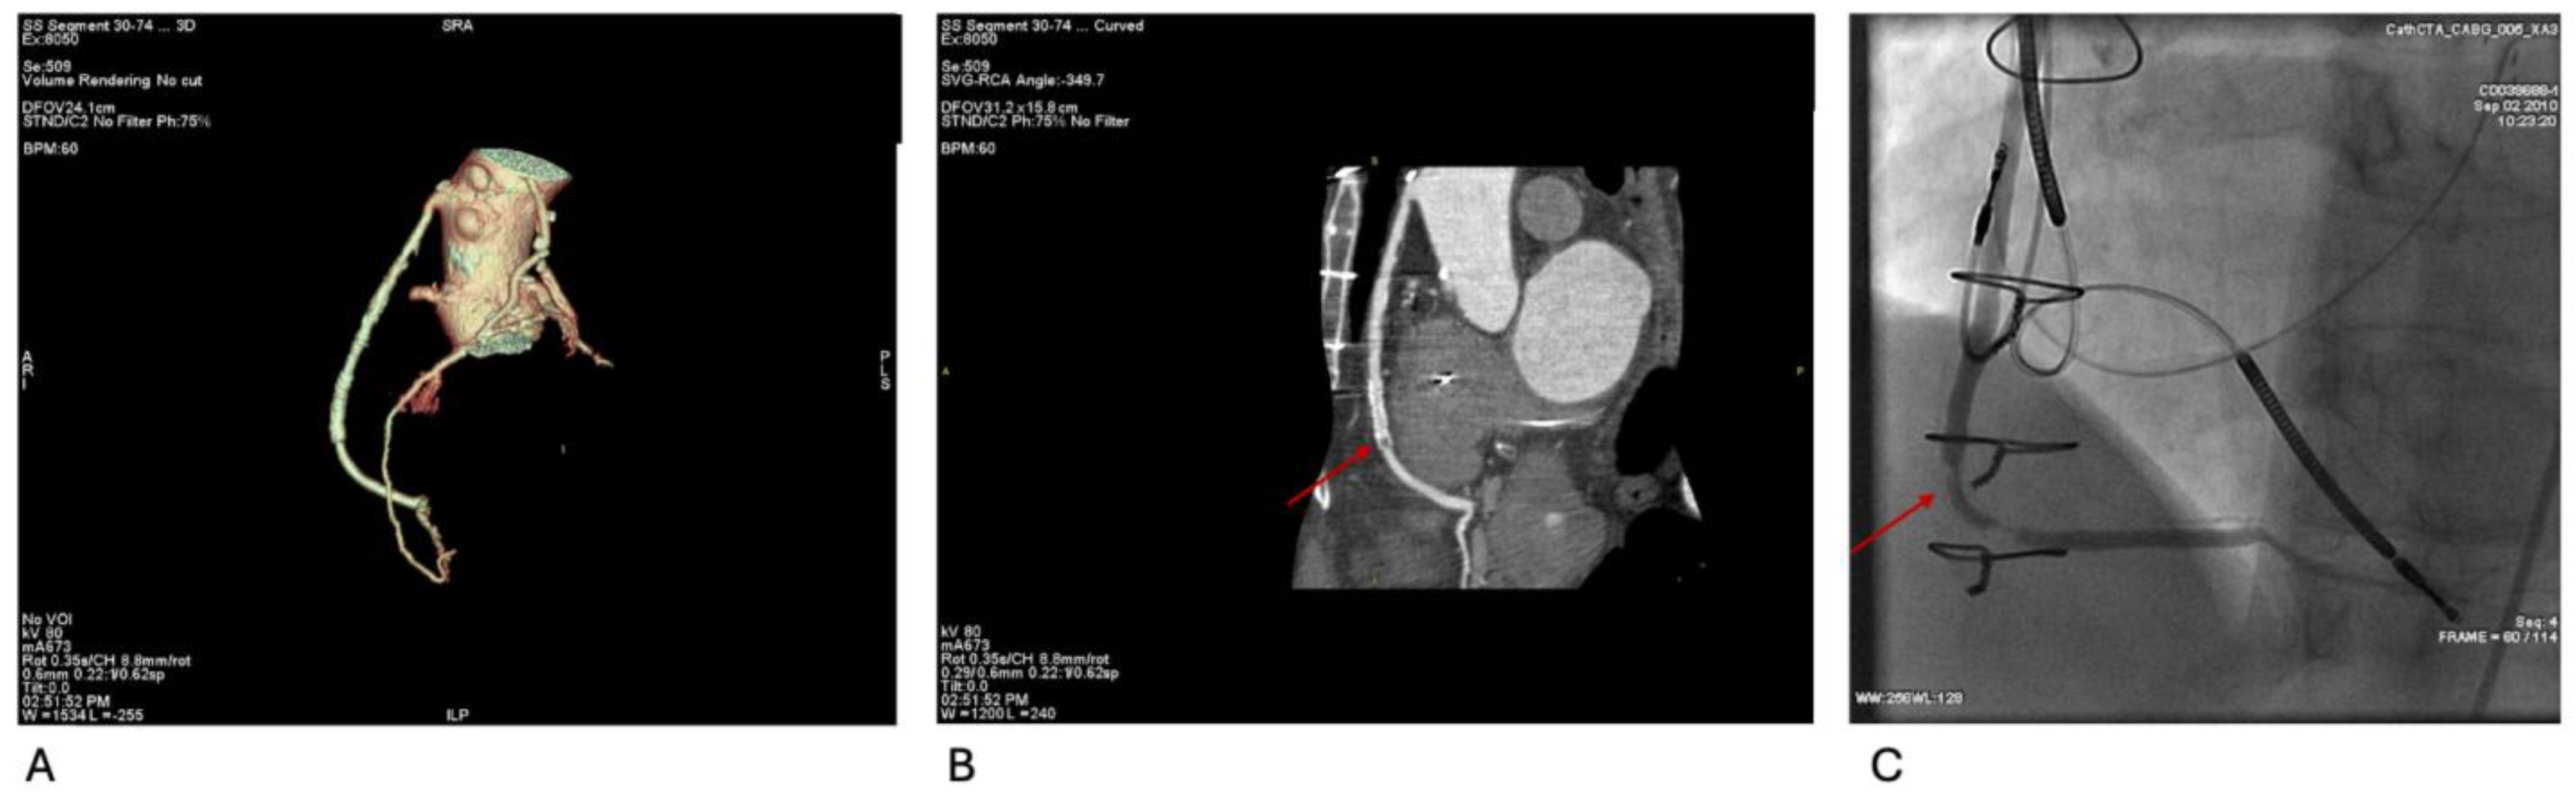

Figure 4A–C illustrate the evaluation of complex CABG anatomy and identification of in-stent restenosis via CCTA and confirmatory angiography. This supports CCTA’s utility in post-revascularization assessment.

Figure 4. (A) Volume-rendered CCTA demonstrates three-vessel CABG anatomy: LIMA–LAD graft with a sequential saphenous vein graft emerging from the mid-LIMA to a diagonal branch, and a separate saphenous vein graft from the ascending aorta to the right posterior-descending artery (SVG-rPDA). (B) Curved-planar reconstruction of the SVG-rPDA shows a previously deployed stent with marked distal intraluminal hypoattenuation, consistent with in-stent restenosis (arrow). (C) Coronary angiography corroborates severe in-stent restenosis of the SVG-rPDA (arrow).